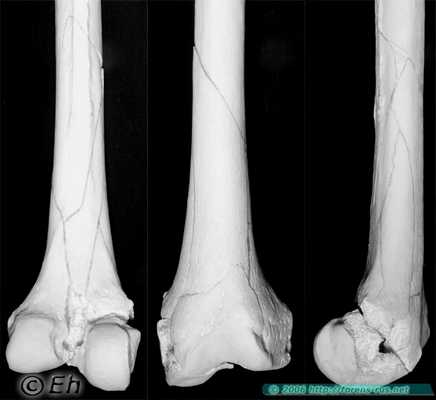

Перелом бедренной кости при переезде колёсами автомобиля

Многооскольчатый перелом нижней трети бедренной кости в результате переезда колёсами грузового автомобиля. Видны следы сложной деформации изгиба с элементами кручения.